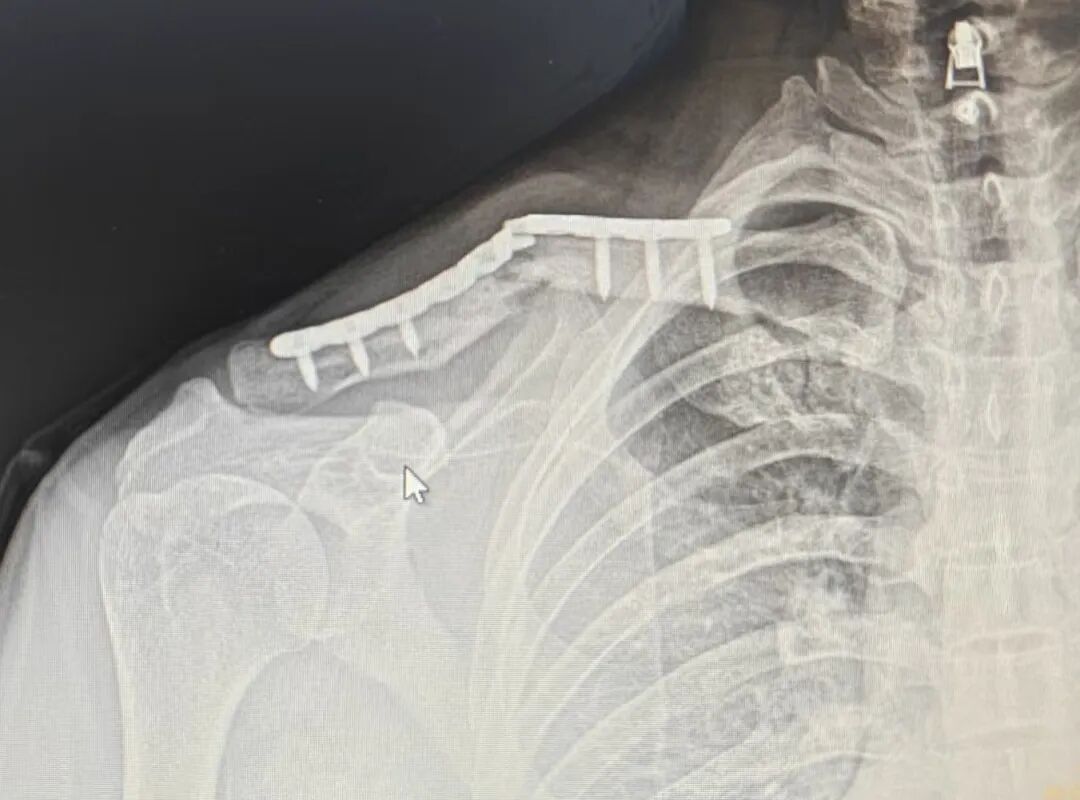

青年男性,锁骨粉碎性骨折

从片子上看

钢板够长,钉子打的也挺好

骨折复位还是不错的

并且没有游离螺钉,没有钢丝